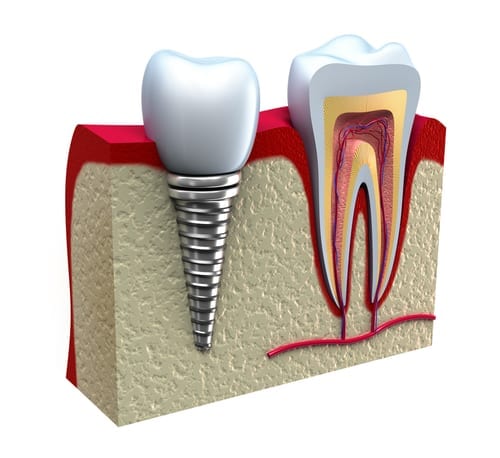

کاشت دندان طبیعی که با نام ایمپلنت دندان نیز شناخته می شود، یک روش جایگزینی دندان از دست رفته است که به علت اینکه یک پایه تیتانیومی دارد که مانند ریشه دندان به استخوان فک جوش می خورد و شباهت زیادی به دندان طبیعی دارد، به نام کاشت دندان طبیعی شناخته می شود.

کاشت دندان طبیعی یا همان ایمپلنت دندان، یکی از پیشرفتهترین روشهای جایگزینی دندانهای از دسترفته است که طی سالهای اخیر با پیشرفت علم دندانپزشکی دیجیتال، دقت و موفقیت آن به طرز چشمگیری افزایش یافته است. در این روش، پایهای از جنس تیتانیوم خالص — که کاملاً با بدن انسان سازگار است — درون استخوان فک کاشته میشود. این پایه همانند ریشهی دندان طبیعی عمل میکند و پس از جوش خوردن کامل با استخوان فک (فرایندی به نام اُسیوانتگریشن)، تاج یا روکش دندان روی آن قرار میگیرد. نتیجه نهایی، دندانی است که از نظر زیبایی، عملکرد و حس جویدن، تقریباً تفاوتی با دندان واقعی ندارد.

کاشت دندان طبیعی میتواند جایگزینی دائمی و بدون نیاز به تراش دندانهای مجاور باشد. برخلاف روشهای قدیمی مانند بریج، ایمپلنت باعث تحلیل استخوان فک نمیشود و حتی به حفظ تراکم استخوان نیز کمک میکند. همین ویژگی باعث شده که این روش، محبوبترین درمان برای دندانهای از دسترفته در سراسر دنیا باشد.